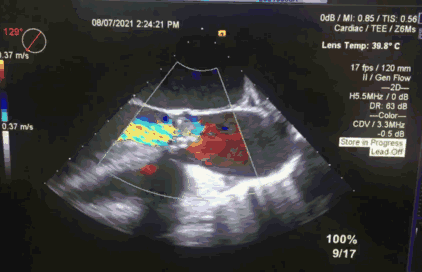

2.术前冠脉造影,提示左冠中段存在狭窄,TEE 见大量反流影;

在释放末段,通过牵拉冠脉支架完成 TAVR-烟囱支架置入术。术后即时造影示少量瓣周漏,测量跨瓣压差示平均压差 12mmHg。经讨论,考虑到冠脉支架与瓣膜自膨胀支架可能存在接触间隙,遂行球囊后扩。后扩后跨瓣压差进一步降低,得到理想的手术效果。